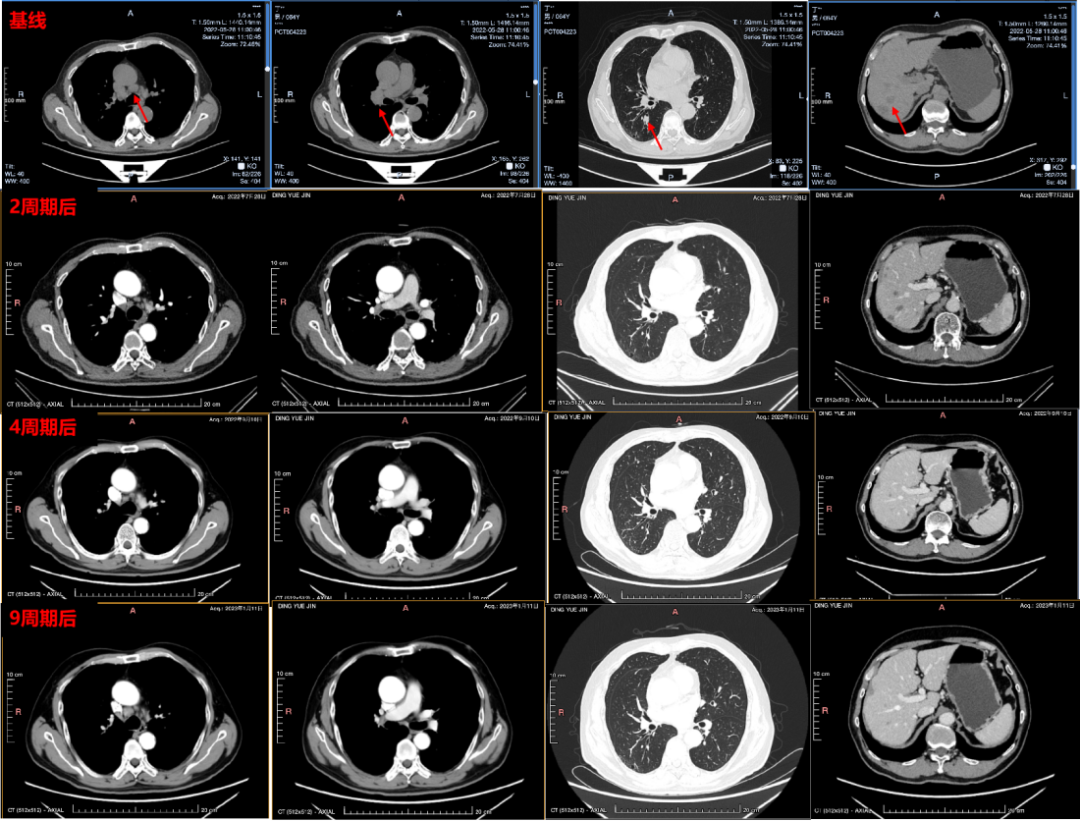

疗效评估:2周期后、4周期后、9周期后分别行胸腹部CT,肺内原发灶及肝转移灶持续缩小,疗效评估均为PR。

影像学检查图像

在治疗过程中,我们密切关注患者的治疗反应。在免疫联合化疗2周期后患者即实现PR,其肺内原发灶及肝转移灶即缩小,4周期后病灶持续缩小,展现了免疫联合化疗对ES-SCLC患者显著的治疗效果。在后续免疫维持治疗期间,患者总体疗效评估仍为PR,实现了长达3余年的PFS。患者不仅在影像学上表现出持续缓解,其生活质量也显著提升,PS评分保持0分,可正常生活和工作,体现了免疫治疗在深度缓解和功能恢复方面的双重优势。